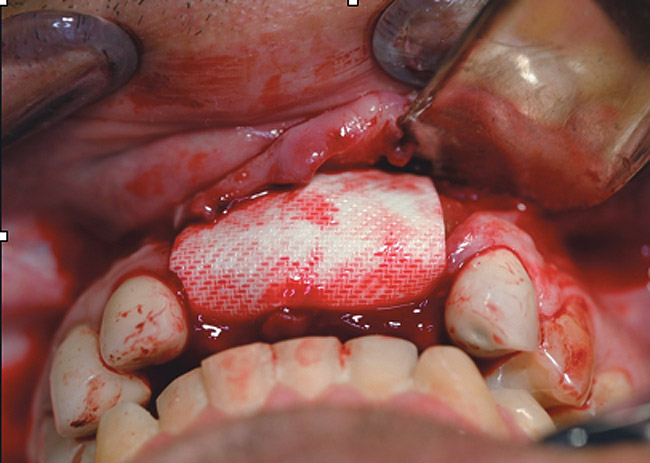

RegenerOss™ Allograft Putty (BIOMET 3i™, www.biomet3i.com) was molded to form the contours of the desired future ridge (Figure 3), and a 20-mm x 30-mm Ossix® Plus membrane (Colbar LifeScience, Ltd, Herzlya, Israel) was trimmed and adapted to cover the graft material (Figure 4). Periosteal relaxing incisions were made, and passive primary closure was obtained.

Figure 4  The Ossix Plus resorbable collagen membrane in place.

Figure 4